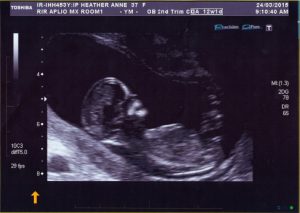

An exciting pregnancy announcement of a different kind! Jason and I will welcome another little human family member in October. Our baby girl is due right in the middle of the busiest time of the breeding season, so it will be a challenging season ahead!